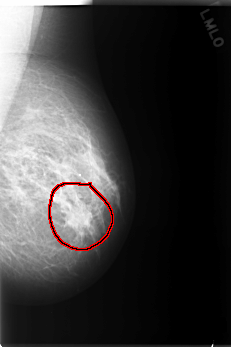

C_0116_1.LEFT_CC

LEFT_CC LINES 5968 PIXELS_PER_LINE 3632 BITS_PER_PIXEL 12 RESOLUTION 50 OVERLAY

FILE: C_0116_1.LEFT_CC.OVERLAY

TOTAL_ABNORMALITIES 1

ABNORMALITY 1

LESION_TYPE MASS SHAPE IRREGULAR MARGINS SPICULATED

ASSESSMENT 5

SUBTLETY 5

PATHOLOGY MALIGNANT

TOTAL_OUTLINES 1

BOUNDARY